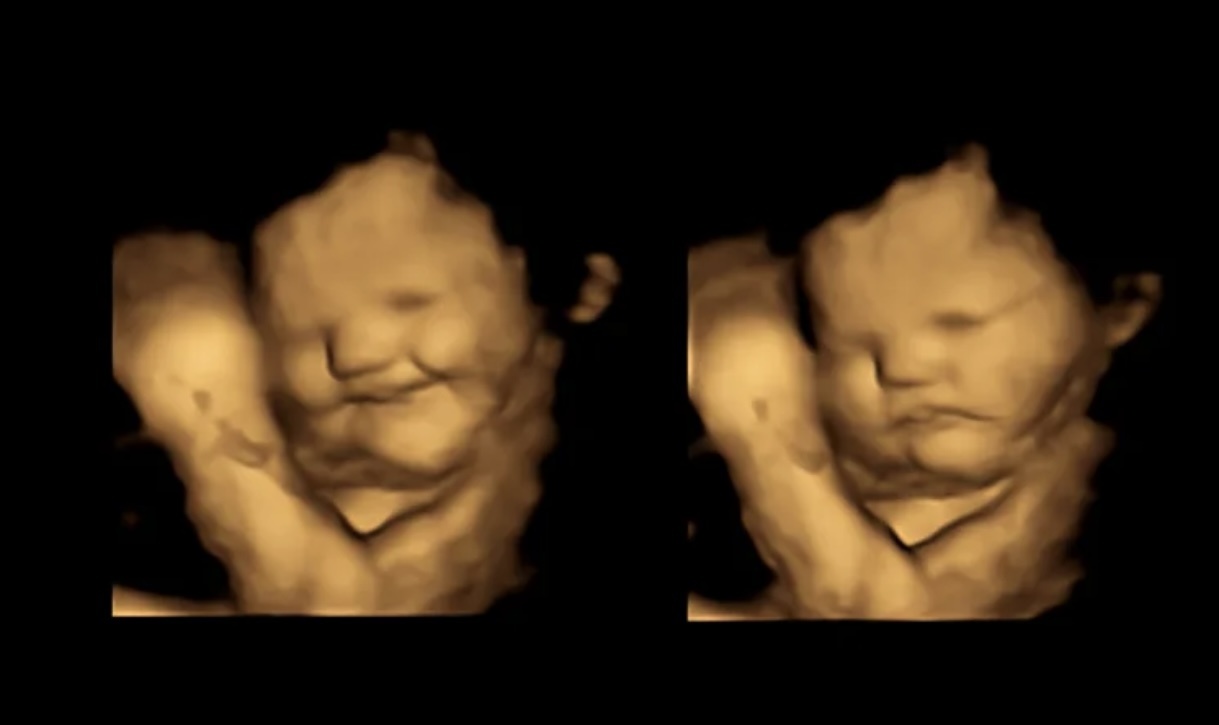

Theo nghiên cứu mới, thai nhi trong bụng mẹ biểu hiện cau có sau khi mẹ ăn cải xoăn nhưng lại mỉm cười sau khi mẹ ăn cà rốt.